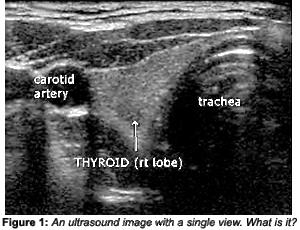

A 2-D image is constructed by "rocking" the probe from side to side, which alters the angle of the beam, giving a slightly different view of a region. At the same time, the probe is moved horizontally across the body. This is not a technique one can acquire in a few minutes; it takes some practice to obtain a diagnostic image. A significant amount of data needs to be processed to produce an image. As you can imagine, the image can change drastically, depending on the technical ability of the person manipulating the probe. Imaging technology is improving, but it still takes a skilled specialist to interpret the findings. In Figure 1, without knowing the location of this image and how it was obtained, it is just a grayscale study; what it is exactly is anyone's guess.

At this point in our discussion, it is not important to know what part of the anatomy this image represents, but suffice to say, it is not an imaging modality easily comprehended by the untrained eye. However, there are more sophisticated versions of 2-D B-scans, including real-time B-scans and 3-D imaging, which make viewing and evaluating the anatomy much easier. (see Figure 2.)